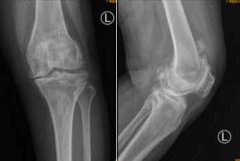

广东首例AI辅助全膝关节置换手术,手术过后就能

南都讯 记者李春花 通讯员 王慧 75岁的何阿姨,常年受到双膝关节疼痛的折磨,近日疼痛愈加严重,双侧膝关节逐渐弯曲变形,辗转来到广医三院关节外科...